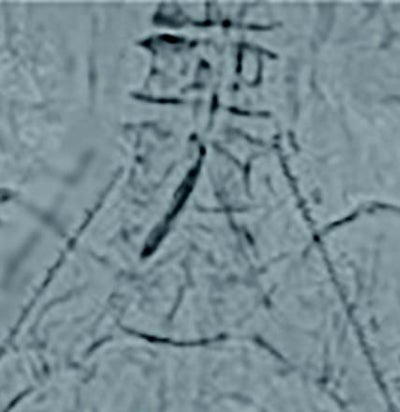

両側橈骨動脈より順行性に両側CIAにガイドワイヤーを通過させた。病変は偏心性石灰化でバルーン拡張により血管破裂のリスクがあることからVBXステントグラフト7.0 × 79 mm(6 Fr)を選択した。両側橈骨動脈からのアプローチにより(図4)スコアリングバルーンによる前拡張後(図5,6)、VBXステントグラフトを留置し(図4,7)、後拡張として高耐圧バルーン8.0 × 40 mmでキッシングバルーンテクニック(KBT)を行った(図8)。この際に迷走神経反射により心拍数が39回/分となったことから、これ以上の径での拡張は危険と判断し、手技を終了した。VBXステントグラフト留置後(図9)と術後造影(図3)では良好な血流が確認された。